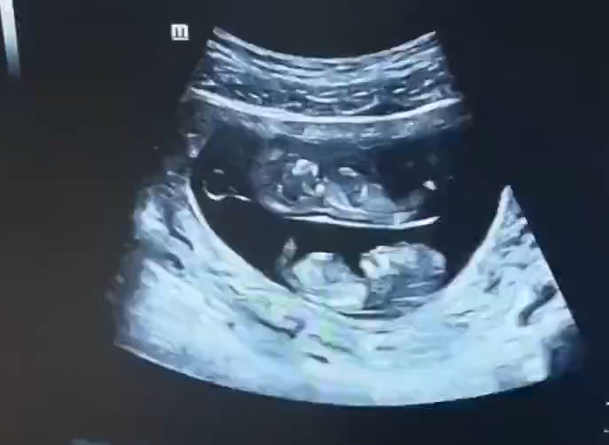

孕妇做B超拍到上下铺宝宝 网友:真·睡在我上铺的兄弟

9月3日,河南的一位孕妇妈妈晒出了一对双胞胎宝宝的B超照片,简直逗笑了一群人!这对宝宝的B超图画风有点不一样哦。

首先,让我们来欣赏一下这对萌萌哒的双胞胎。画面上,有两颗宝宝的小脑袋,一颗在上面,一颗在下面,就像是他们自己在母亲的肚子里订了上下铺一样。当这张照片被晒出后,网友们纷纷惊呼:“原来双胞胎还有上下铺啊,还以为都是大通铺!” 看来大家对于双胞胎的构造有了全新的认识!